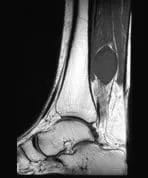

Posterior Tibial Neuroma

A patient presents with swelling in the right calf above the ankle.

Findings

The sagittal MR images demonstrate a well-defined lobulated mass in the posterior compartment of the right calf. The lesion enhances after contrast and the features are suggestive of a posterior tibial neuroma.